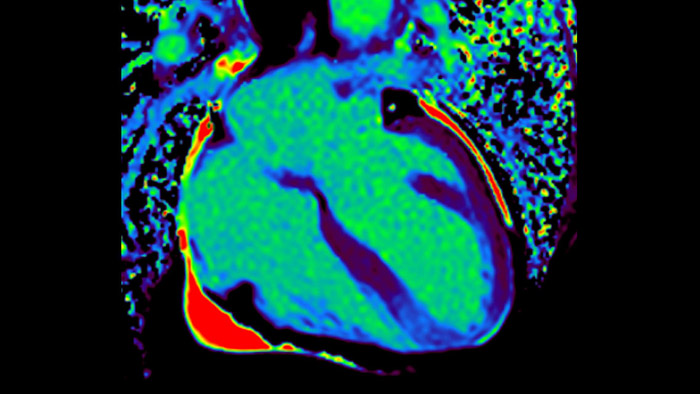

IntelliSpace Portal MR Caas5,6 Strain7 assists in patient diagnosis and monitoring by providing global strain parameters such as global longitudinal strain (GLS), global circumferential strain (GCS), and global radial strain (GRS), using short and long axis MR images, as well as describing the myocardium deformation- such as shortening, thickening, and lengthening during the cardiac cycle.

Today's diagnostics often cannot detect heart dysfunction until symptoms occur. MyoStrain utilises segmental strain to measure 48 segments of the heart and provides physicians with a unique diagnostic tool to help identify regional dysfunction before the heart as a whole is affected.